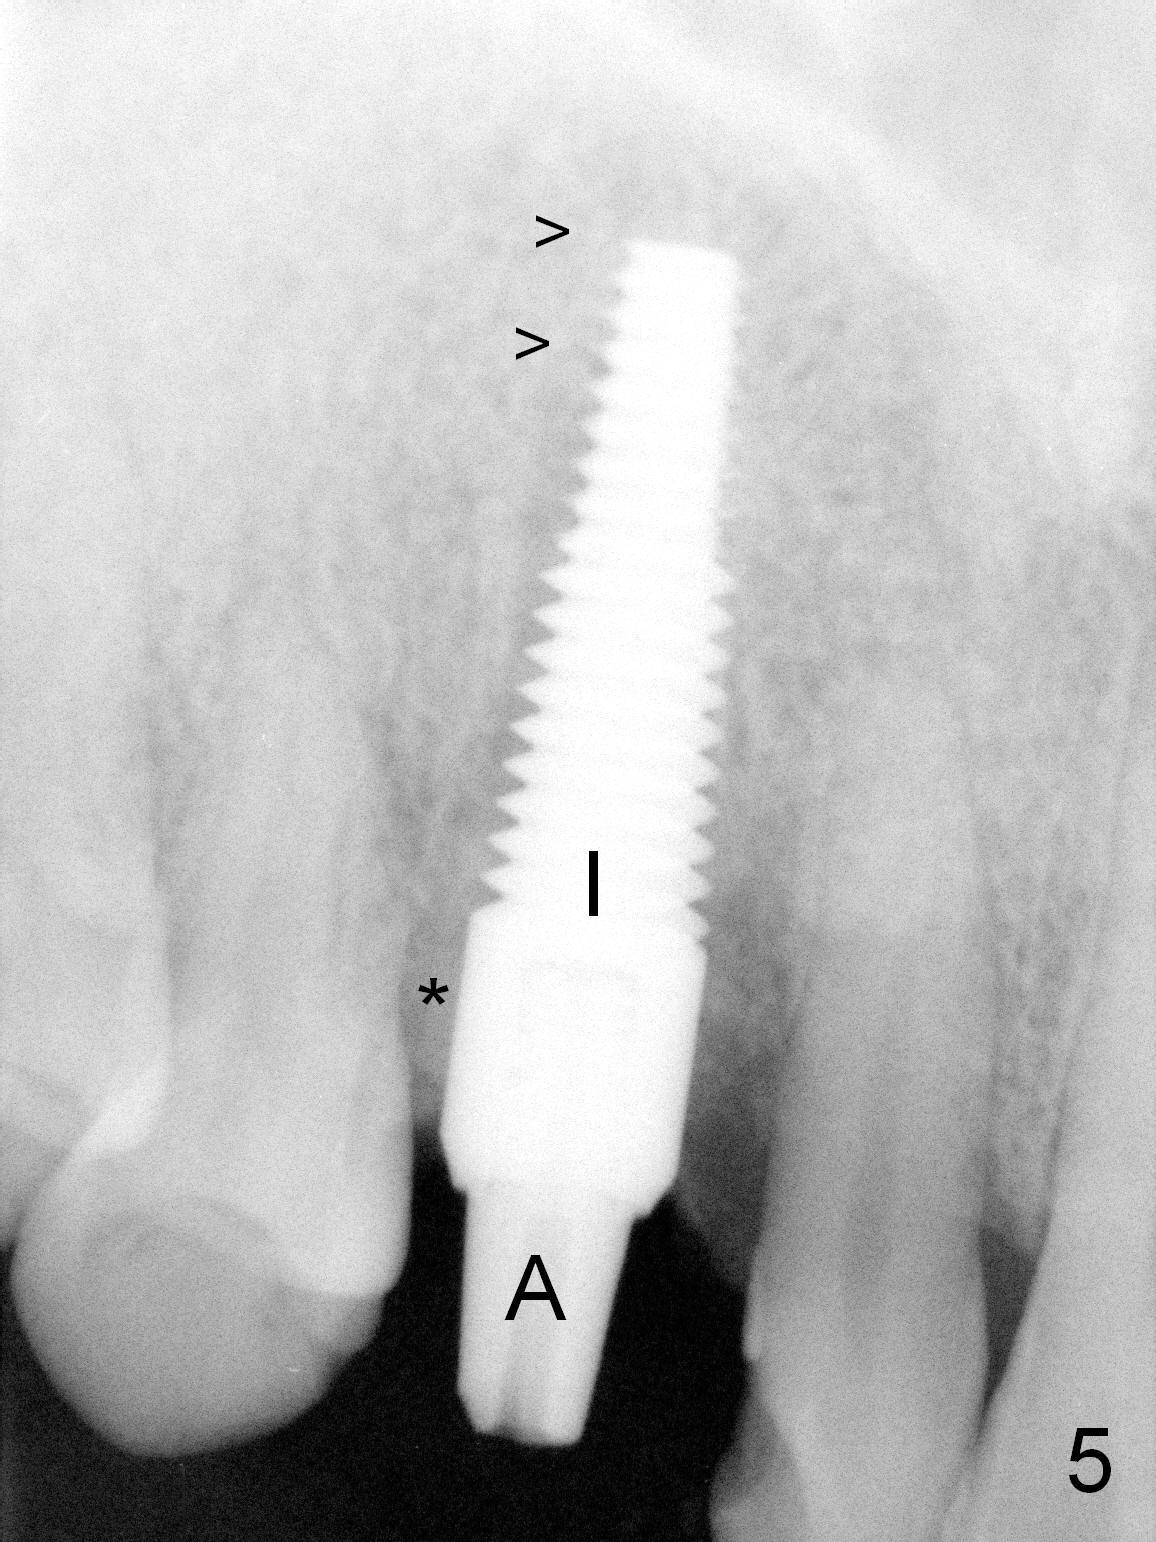

After 5x20 mm implant is placed, the distal gap is filled with bone graft (Fig.5 *). An abutment is placed (A) for fabrication of an immediate provisional (Fig.6 P). The latter hold the labial gingiva bulging (Fig.6 >). When the provisional is removed for bone grafting, the labial gingiva collapses (Fig.7 arrowheads). In fact a piece of cone-shaped Osteotape (Impladent) is placed palatal to the labial gingiva/thin labial plate and a small amount of graft is placed in the deepest area of the socket (labial to the osteotomy) prior to placement of the implant. More graft is placed in the peri-implant gap, particularly labially to keep the labial gingiva convex (Fig.8 arrowheads). The lacerated gingiva is to be approximated with perio glue (Fig.9 <). Collagen dressing is placed over the exposed graft before cementation of the provisional. Perio dressing is applied for further protection and seal.